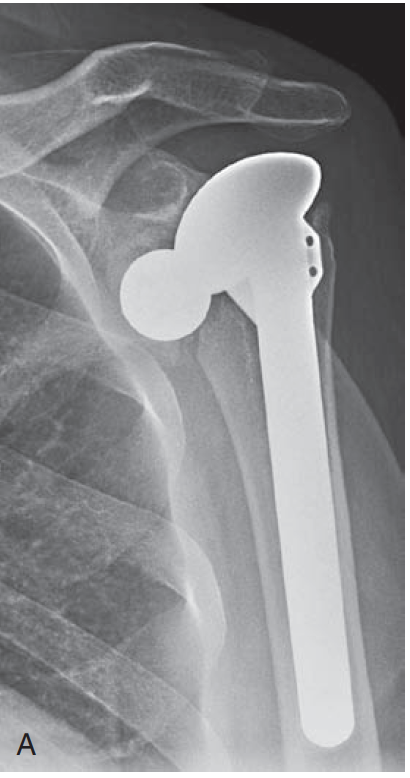

One of the most common errors is a "too-high" position, as shown below.

Too high positioning of the humeral head can result from a too high neck cut

or from failure to properly seat the component

We like to be sure that the margin of the humeral prosthesis is just below the "berm" as shown below.